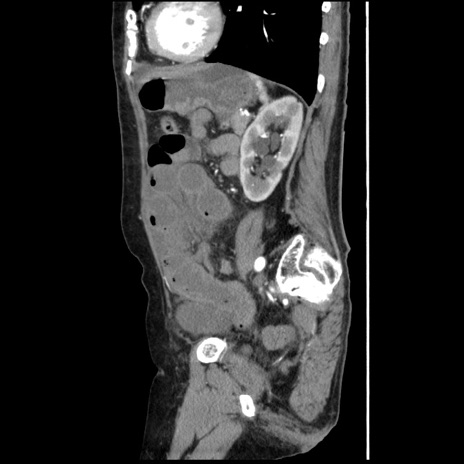

症例1(矢状断像)

【症例】80歳代女性

【主訴】腹痛

【現病歴】8時間前から腹痛あり来院。

【既往歴】糖尿病、脂質異常症、子宮体癌にて子宮全摘術

【身体所見】意識清明・会話良好だが腹痛で苦悶様、全腹部にわたって反跳痛と圧痛あり

【データ】WBC 13600、CRP 0.14、LDH 224、CK 90